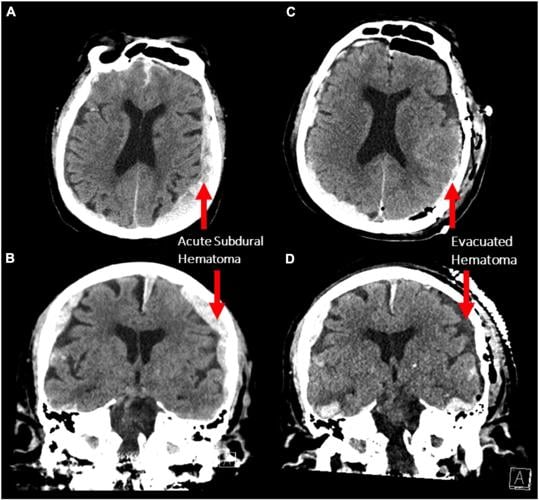

IMAGING FROM PATIENT WHO DIED DURING RECORDING OF BRAIN WAVES

Scan of the brain of the patient in Vancouver who was being monitored for seizures when the patient passed away.Ā  Image courtesy Frontiers in Aging Neuroscience.Ā Ā